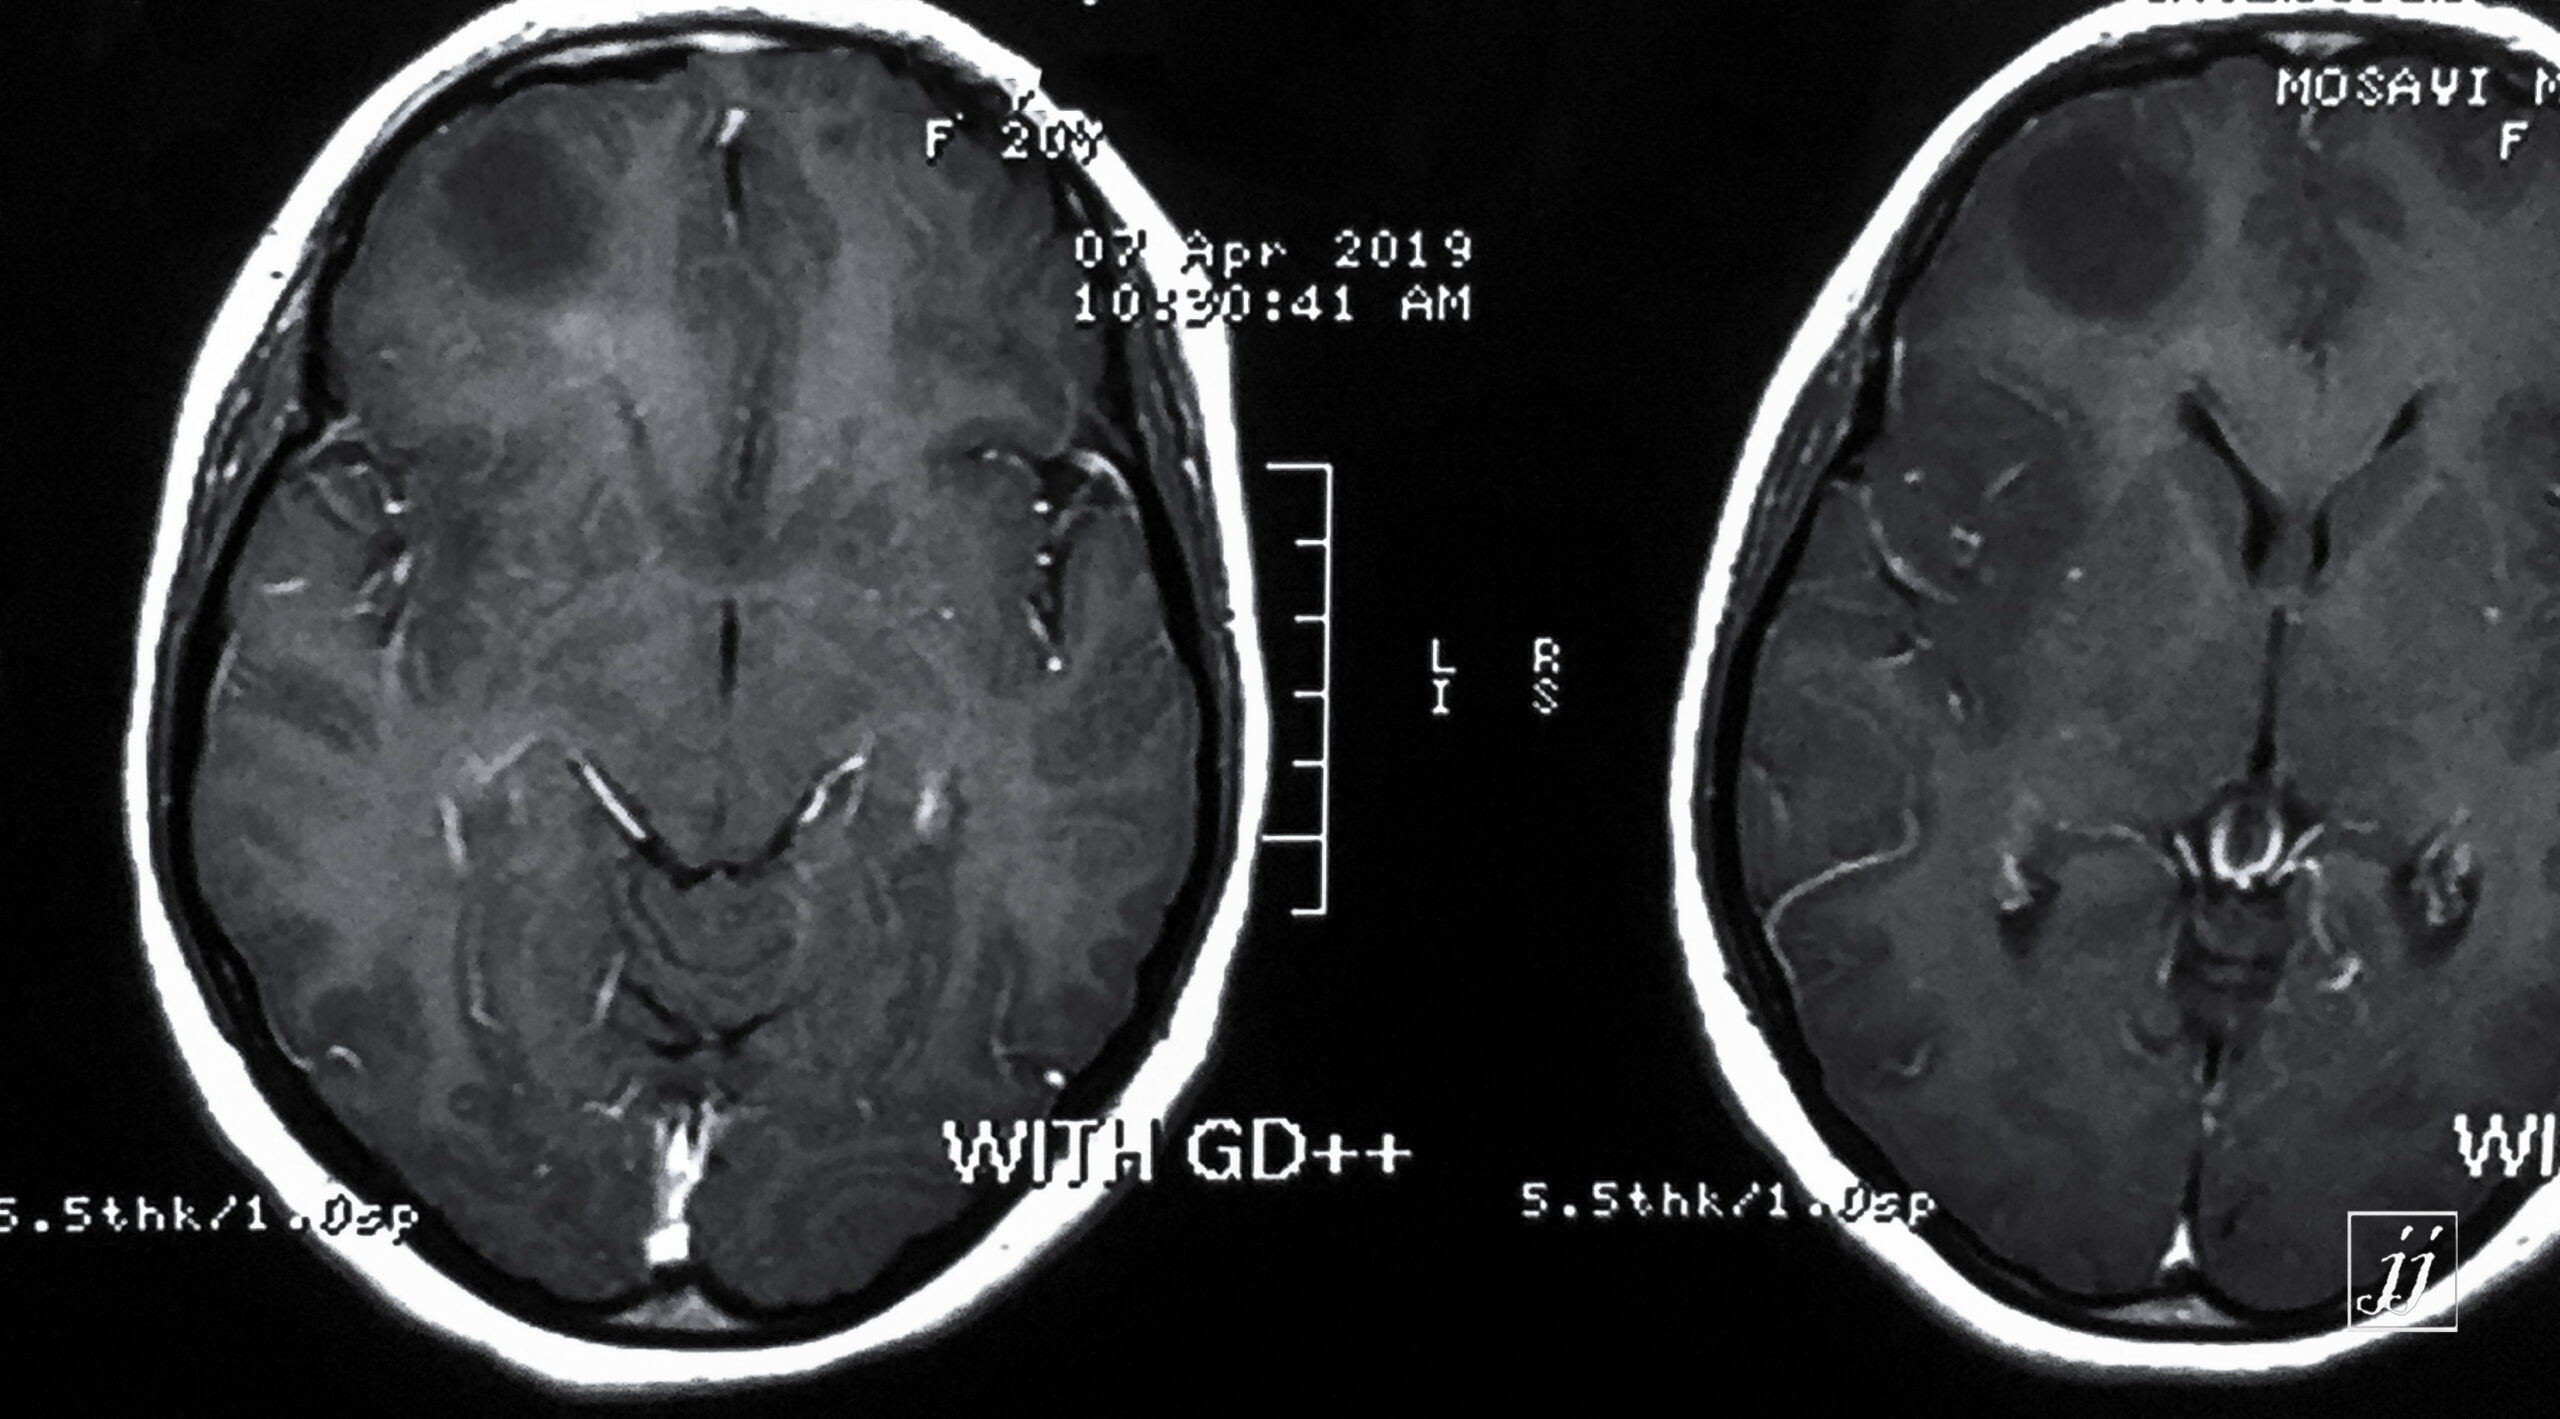

Brain- right frontal astrocytoma (5)